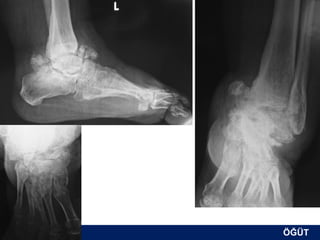

OLGU No 3

FK, 58y, ♂

2,5 ay sonra

ÖĞÜT

Erken postop